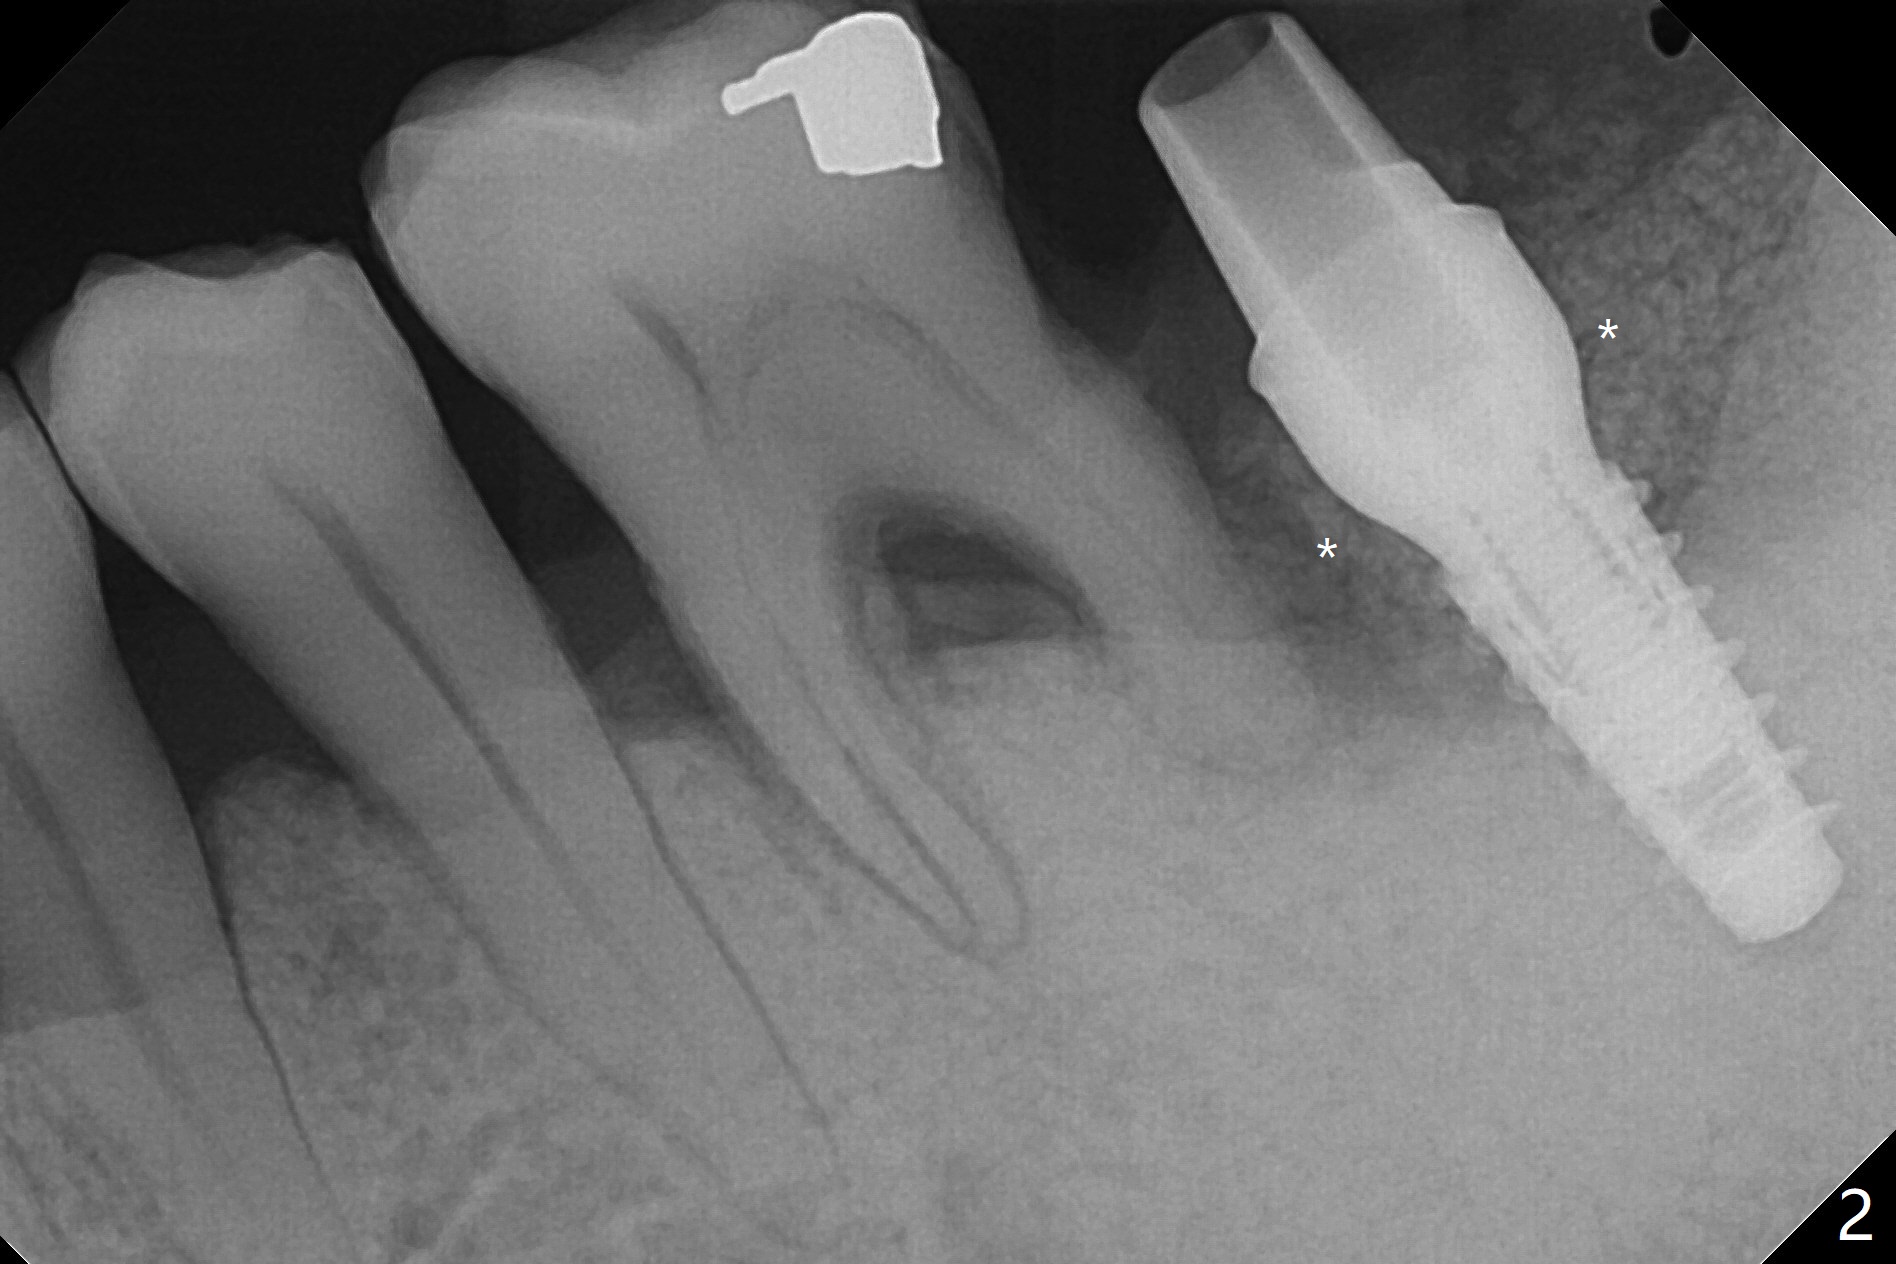

下颌第二磨牙严重骨质吸收翻瓣种植,视野挺不好,多亏导板,植入勉强过关(图一),由于植入大量粘性骨粉(图二:*)和两张PRF膜,近中舌侧切口缝合困难,使用树脂敷料固定。